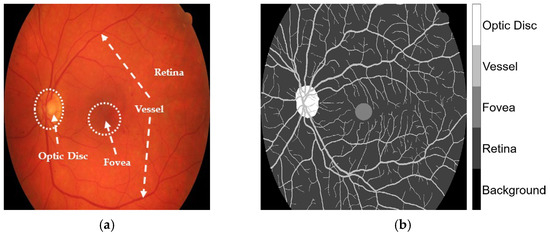

The HRF, DRIVE, and CHASE_DB1 datasets facilitated the examination of label inaccuracies within the CLA framework. The ground truths were first modified by incorporating three additional classes, retina, optic disc, and fovea, as shown in Figure 1. The revised annotations were conducted under the guidance of seasoned ophthalmologists who delivered precise delineations to guarantee accuracy in the segmentation methodology. When these three classes were overlaid, they became major anatomic structures in the retinal images. Blood vessels in the STARE database were manually annotated by two experts, Adam Hoover (AH) and Valentina Kouznetsova (VK), as referenced in [10]. The annotated data are publicly available at https://cecas.clemson.edu/~ahoover/stare/probing/index.html (accessed on 2 July 2025). These annotations are used as reference labels to evaluate label rectification within the PBNR framework.

Figure 1. Example from the HRF dataset: (a) original retinal image, Image1024-02_g; and (b) corresponding ground truth annotation.